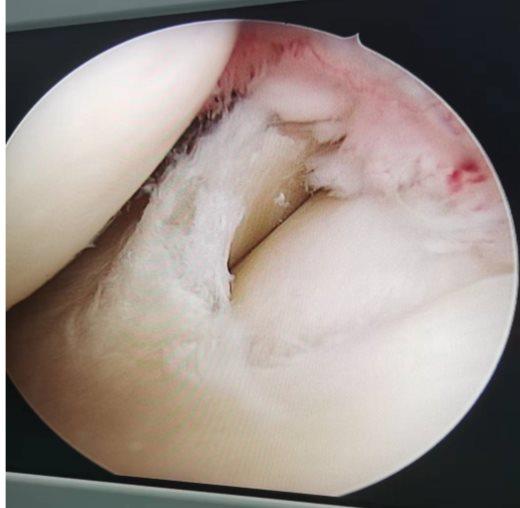

关节镜手术主要是把撕裂的半月板修整成形,并不是把整个半月板都切除掉。手术是最大程度地恢复半月板的功能,把撕裂的半月板对膝关节造成的损伤减小到最低。膝关节镜微创是治疗膝关节半月板损伤的主流手术,具有创伤小,恢复快,住院时间短,手术风险小的特点。

半月板Ⅲ度损伤